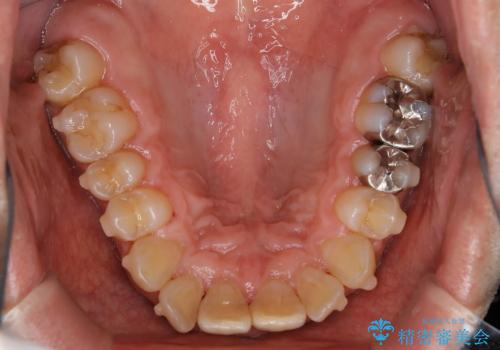

しぶといステインもエアフローワンで1日でキレイに!!

- インビザラインの治療中ですが、歯石やステインが気になるとのことでした。

コーヒーが大好きでよく飲むそうです。

全体的に歯石やステインが付着していたため、エアフロー60分コースを行いました。